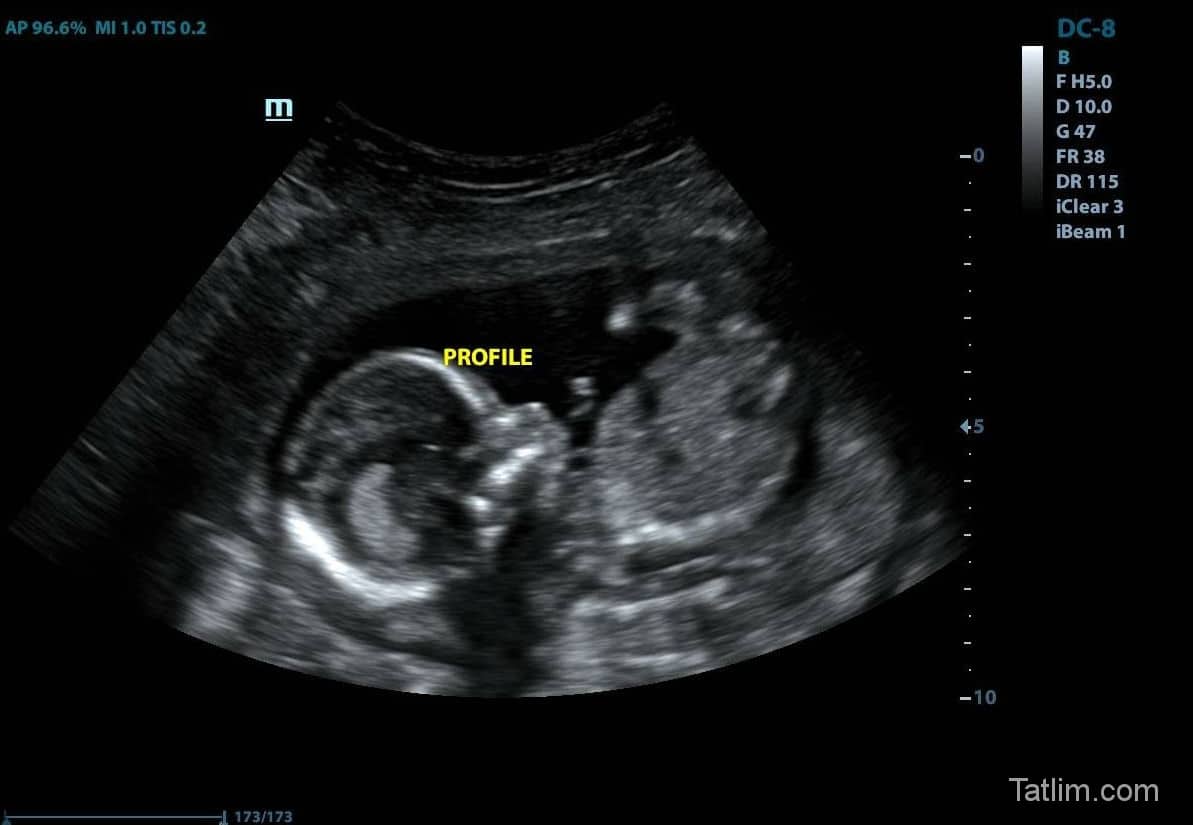

29 haftalık bebek ultrason görüntülerinde baş aşağı pozisyonda görüntülenebilir. Her geçen hafta bebeğiniz size kendini daha fazla hissettiriyor. 22 mart 2019 hamilelik dönemi genel kategorisinde nazangül (72 puan) sordu. Meme dokusu, prolaktin denilen bir hormon aracılığı ile süt üretimi yapar. 29 haftalık gebelik (hamilelik) görüntüsü, gebelikte 29. Her bebeğin kendine has bir gelişim çizgisi olsa da, gebelik haftasına göre bu ortalamalar alınır.

Haftada hala baş aşağı pozisyona gelmiş olmayabilmektedir. Haftada bebeğin boyu ve kilosu ne kadar? 29 haftalık bebek ultrason görüntülerinde baş aşağı pozisyonda görüntülenebilir.

hamilelikte29haftaultrasongoruntusu1 Tatlım

29 haftalık bebek ultrason görüntülerinde baş aşağı pozisyonda görüntülenebilir. Bu dönemle beraber bebek çok hızlı bir şekilde kilo almaya başlar. Bu hafta bebek neredeyse doğacak bir bebek boyutuna gelmiştir.

hamilelikte29hafta2 Tatlım

Kızlar 29 haftalık bebek kilosu ne kadardı bizim ki geride geliyor ne yapsam. 29 haftalık bebek ultrason görüntülerinde baş aşağı pozisyonda görüntülenebilir. Tabi ki ebeveynlerin anne rahmindeki yavruları ile ilgili en çok merak ettikleri konulardan biri bebeğin kütle ve uzunluk bilgisidir.